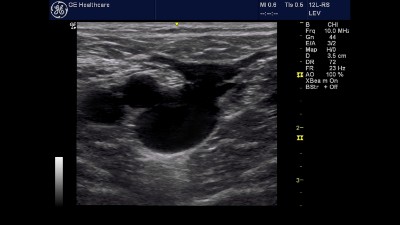

Zweidimensionale Ultraschallverfahren – Bei diesem Ultraschallverfahren handelt es sich um eine herkömmliche Sonographie, die der Anfertigung von zweidimensionalen Schnittbildern der Venen dient. Im Rahmen der sogenannten Kompressionssonographie wird das venöse Gefäß bzw. sein Lumen auf die Komprimierbarkeit hin untersucht. Das Verfahren wird zur Diagnose von Venenthrombosen eingesetzt und hat eine hohe Treffsicherheit. Ein thrombosierter Venenabschnitt ist kaum oder auch gar nicht komprimierbar.

Duplexsonographie (= Kombination aus B-Bild mit PW-Doppler/Pulse Wave Doppler) – Diese Ultraschalluntersuchung ist ein Kombination aus einem zweidimensionalen Ultraschallverfahren und einer Dopplersonographie (bei der Dopplersonographie handelt es sich um ein sonographisches Verfahren, das Flüssigkeitsströme (vor allem den Blutfluss) dynamisch darstellen kann). Die Duplexsonographie ermöglicht die Diagnose von Venenklappeninsuffizienzen und die Erfassung von Thromben und deren räumliche Lokalisation.

Farbduplexsonographie – Dieses Verfahren ähnelt funktionell der bereits beschriebenen Duplexsonographie, allerdings ermöglicht eine technische Veränderung die farbliche Darstellung von Strömungen, so dass Turbulenzen oder Refluxströmungen eindeutiger darzustellen sind. Mit diesem aktuell modernsten und portablem Gerät wird in der Praxis die Venendiagnostik durchgeführt und nach einer vorherigen Doppleruntersuchung vervollständigt. Die Farbduplexsonographie wird vor allem bei venösen Gefäßen im Bereich des Unterschenkels eingesetzt.